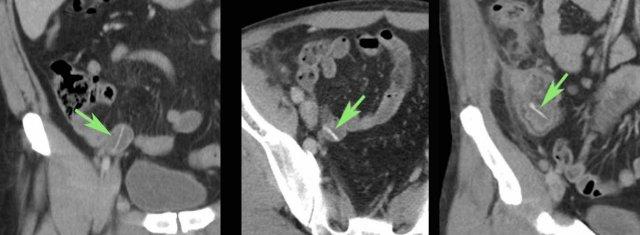

Bệnh nhân nam 85 tuổi này nhập viện với đau khu trú dữ dội, viêm phúc mạc khu trú và CRP 200, lâm sàng nghi ngờ viêm ruột thừa.

Siêu âm cho thấy một vùng nhỏ khu trú gồm mỡ tăng âm bị viêm (đầu mũi tên), chứa một ít dịch (*) và một phản âm khó lý giải (mũi tên trắng).

Chẩn đoán siêu âm dự kiến là viêm phần phụ mạc nối với vùng xuất huyết trung tâm nhỏ.

CT xác nhận thâm nhiễm mỡ khu trú và phát hiện thêm một bóng khí cũng như dày thành nhẹ của một quai ruột non lân cận.

Áp dụng từ gợi nhớ PSI-ABCD, tất cả các nguyên nhân đều được loại trừ, ngoại trừ dị vật sắc nhọn.

Sau khi tìm kiếm có chủ đích, một xương cá được phát hiện tại manh tràng (mũi tên xanh lá trên CT).

Rõ ràng, xương cá này đã gây ra thủng, và sau đó được đẩy đi bởi nội dung ruột non. Bệnh nhân được điều trị bằng kháng sinh đơn thuần và hồi phục hoàn toàn.